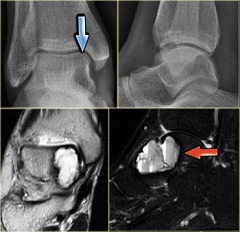

Основными методами диагностики кисты сустава являются:

Данные методы исследования позволяют установить заболевание, ставшее причиной образования кисты, выявить степень поражения сустава, определить размер и локализацию кисты сустава в тканях, произвести биохимическое исследование содержимого кистозного образования.